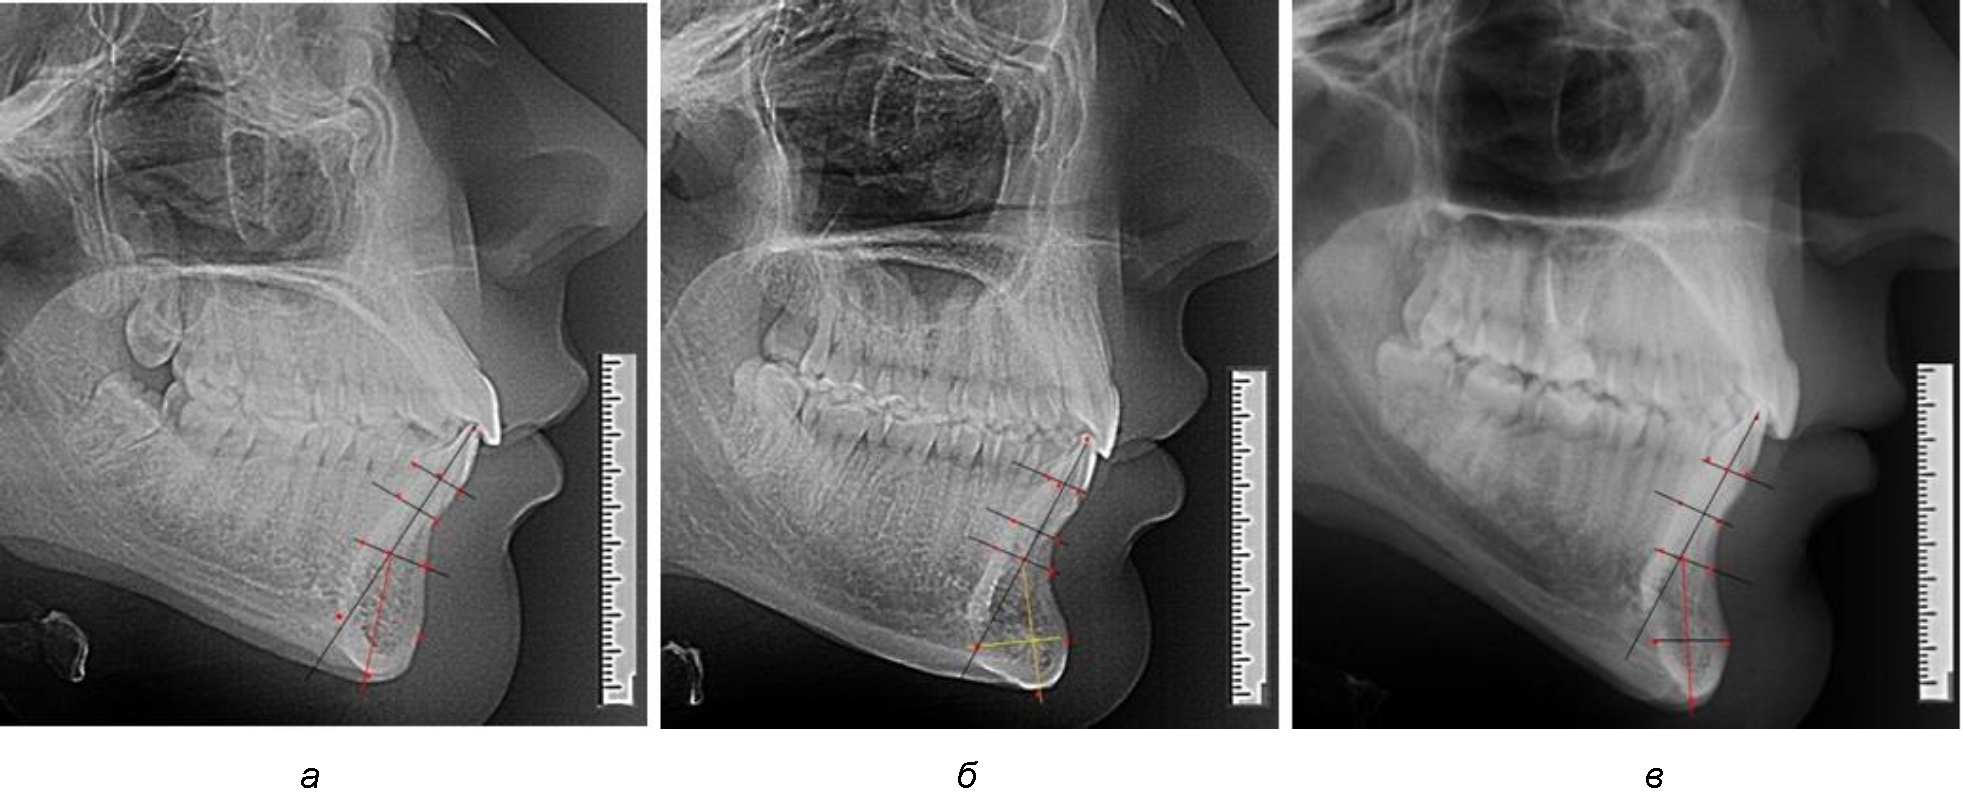

При анализе полученных данных обращает на себя внимание факт того, что из вертикальных параметров зубоальвеолярной части сегмента наиболее вариабельным является размер между апикальными точками Downs и Schwarz (BSM–B), который составлял (6,79 ± 0,54) мм, при величине сигмального отклонения – 2,35. Также большая ошибка репрезентативности и сигмальное отклонение было отмечено при оценки ширины подбородочного выступа. В связи с этим встречались варианты резцовых сегментов нижней челюсти различные как по ширине, так и по высоте, а также по расхождению положения апикальных точек по Downs и Schwarz (рис. 3).

Рис. 3. Варианты среднего (а), широкого (б) и узкого (в) нижнечелюстного резцового сегмента

Варианты резцовых сегментов нижней челюсти различные как по ширине, так и по высоте, а также по расхождению положения апикальных точек по Downs и Schwarz представлены на рис. 4.

Рис. 4. Особенности нижнечелюстного резцового сегмента на ТРГ у людей при среднем (а), широком (б) и узком (в) вариантах